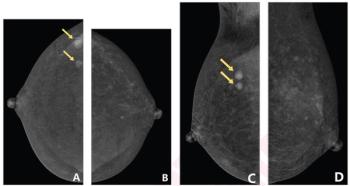

Researchers showed that adjunctive use of a deep learning algorithm resulted in an eight percent increase in sensitivity and a nearly 10 percent increase in specificity for differentiating between colon carcinoma and acute diverticulitis on computed tomography (CT) scans.